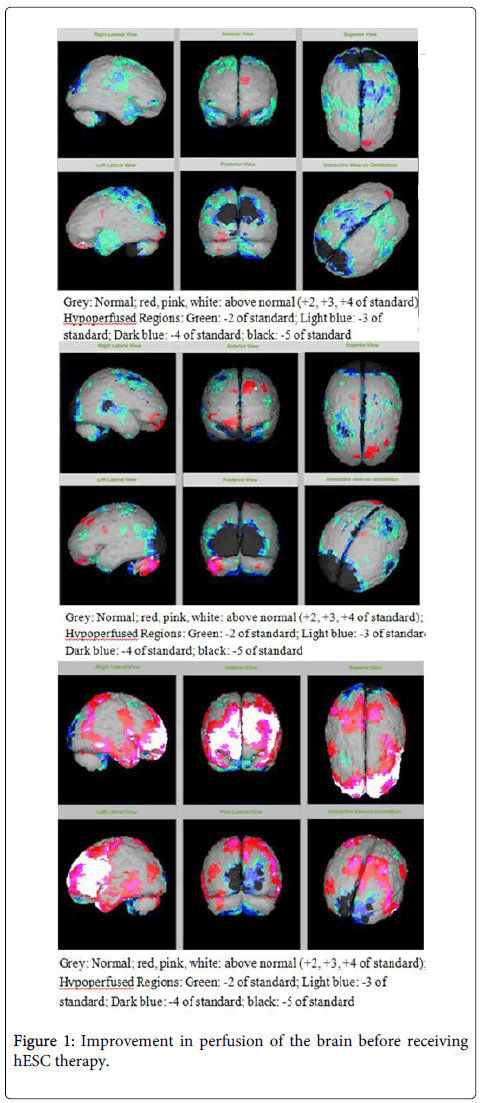

例如,一名被診斷為CP的13歲男孩因認(rèn)知、協(xié)調(diào)性、清晰度較差,無法看、閱讀或看電視,于2011年4月入院。在接受hESC治療后,該兒童的病情有所改善在認(rèn)知方面能夠通過學(xué)校考試,能夠在15厘米以上閱讀,能夠看到顏色,并且能夠看電視。

該患者的SPECT掃描如圖1和2所示。

SPECT掃描

在研究開始和結(jié)束時(shí),23名患者接受了SPECT掃描。在枕葉或額葉或雙葉中觀察到灌注不足。23例接受SPECT掃描的患者中,5例患者表現(xiàn)為枕葉灌注不足,7例患者表現(xiàn)為額葉灌注不足,11例患者表現(xiàn)為枕葉和額葉灌注不足。

總體而言,治療結(jié)束時(shí),2名患者的灌注正常,18名患者(12名男性和6名女性患者)顯示灌注顯著改善(>60%),3名患者顯示灌注中度改善(30-60%)。大多數(shù)在接受hESC治療前額葉和枕葉嚴(yán)重低灌注的患者在接受 hESC 治療后情況有所改善。23名可獲得SPECT掃描報(bào)告的患者的GMFCS評(píng)分在hESC治療后有所改善(表2)。